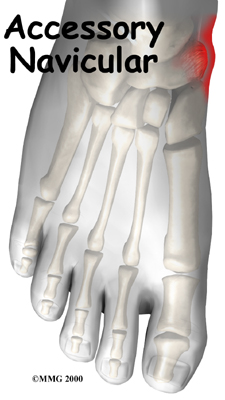

Accessory Navicular Problems

Not everyone has the same number of bones in his feet. It is not uncommon for both the hands and the feet to contain extra small accessory bones, or ossicles, that sometimes cause problems.